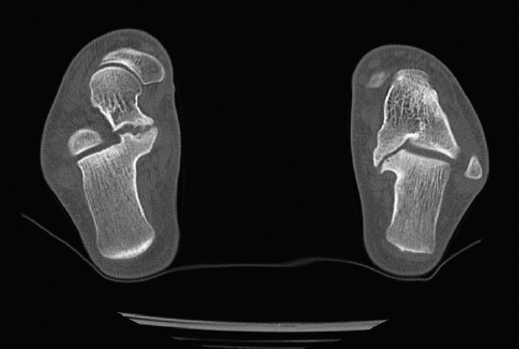

Figura 6. Coalición tarsiana.

Se trata de un caso de Dr. Sobrón, publicado en Foot Ankle International(9), que presenta a un paciente varón de 17 años con pie plano valgo doloroso. Tras la valoración clínica y radiológica, se observa una coalición astragalocalcánea (Figura 6).